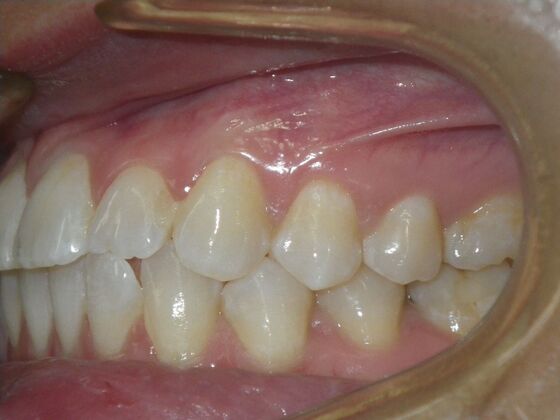

This patient had concerns with the lower anterior teeth. There were some slight rotations and the midline of the lower incisors wasn't lined up with the upper midline. To correct this we used slenderizing of teeth in strategic areas of the lower arch to correct the rotations and line up the midlines. Patient very pleased with the results.